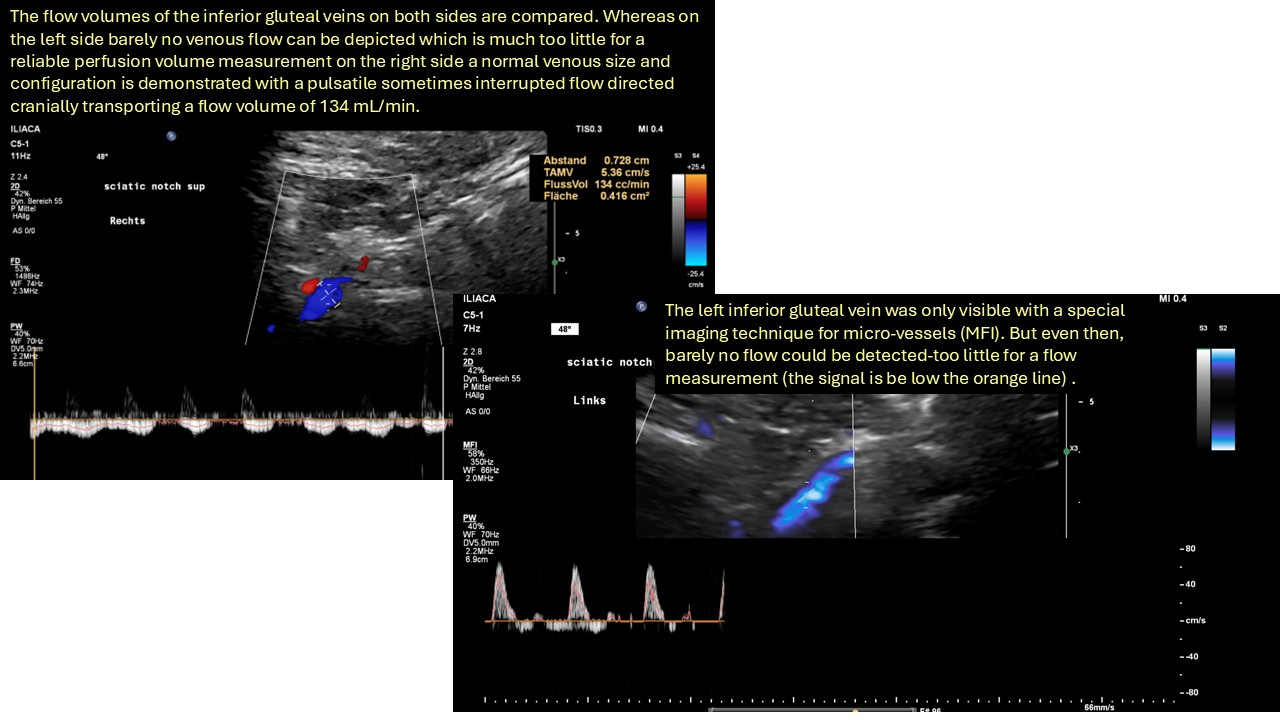

Die spastische Innenrotation des linken Beins wird durch eine venöse Stauung des Rückenmarks im Wirbelkanal verursacht, während die entlang des Ischiasnervs ausstrahlenden Schmerzen durch eine schwere Obstruktion des Abflusses in der linken inneren Beckenvene verursacht werden, die den venösen Rückfluss aus dem Ischiasnerv über die linke untere Gesäßvene fast vollständig stoppt.